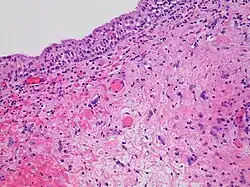

Histopathology of radiation cystitis, including atypical stromal cells ("radiation fibroblasts")

Radiation enteropathy

The gastrointestinal tract can be damaged following abdominal and pelvic radiotherapy.[44] Atrophy, fibrosis and vascular changes produce malabsorption, diarrhea, steatorrhea and bleeding with bile acid diarrhea and vitamin B12 malabsorption commonly found due to ileal involvement. Pelvic radiation disease includes radiation proctitis, producing bleeding, diarrhoea and urgency,[45] and can also cause radiation cystitis when the bladder is affected.